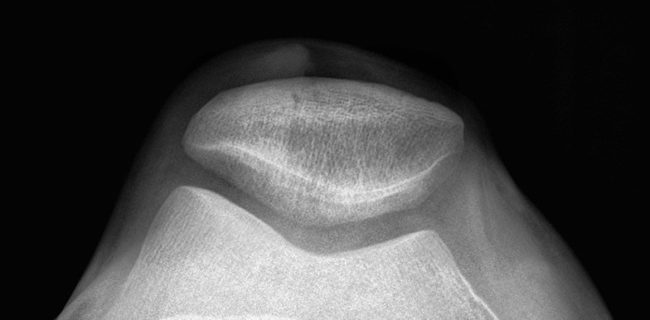

5 Treatments For Knee Pain

Current studies tell us that 19% of the population suffers from some form of knee pain. It appears to affect more women than men with nearly 20% of women reporting pain and only 10-15% of their male counterparts. Knee pain is any pain that affects the knee joint and can result from an injury to…